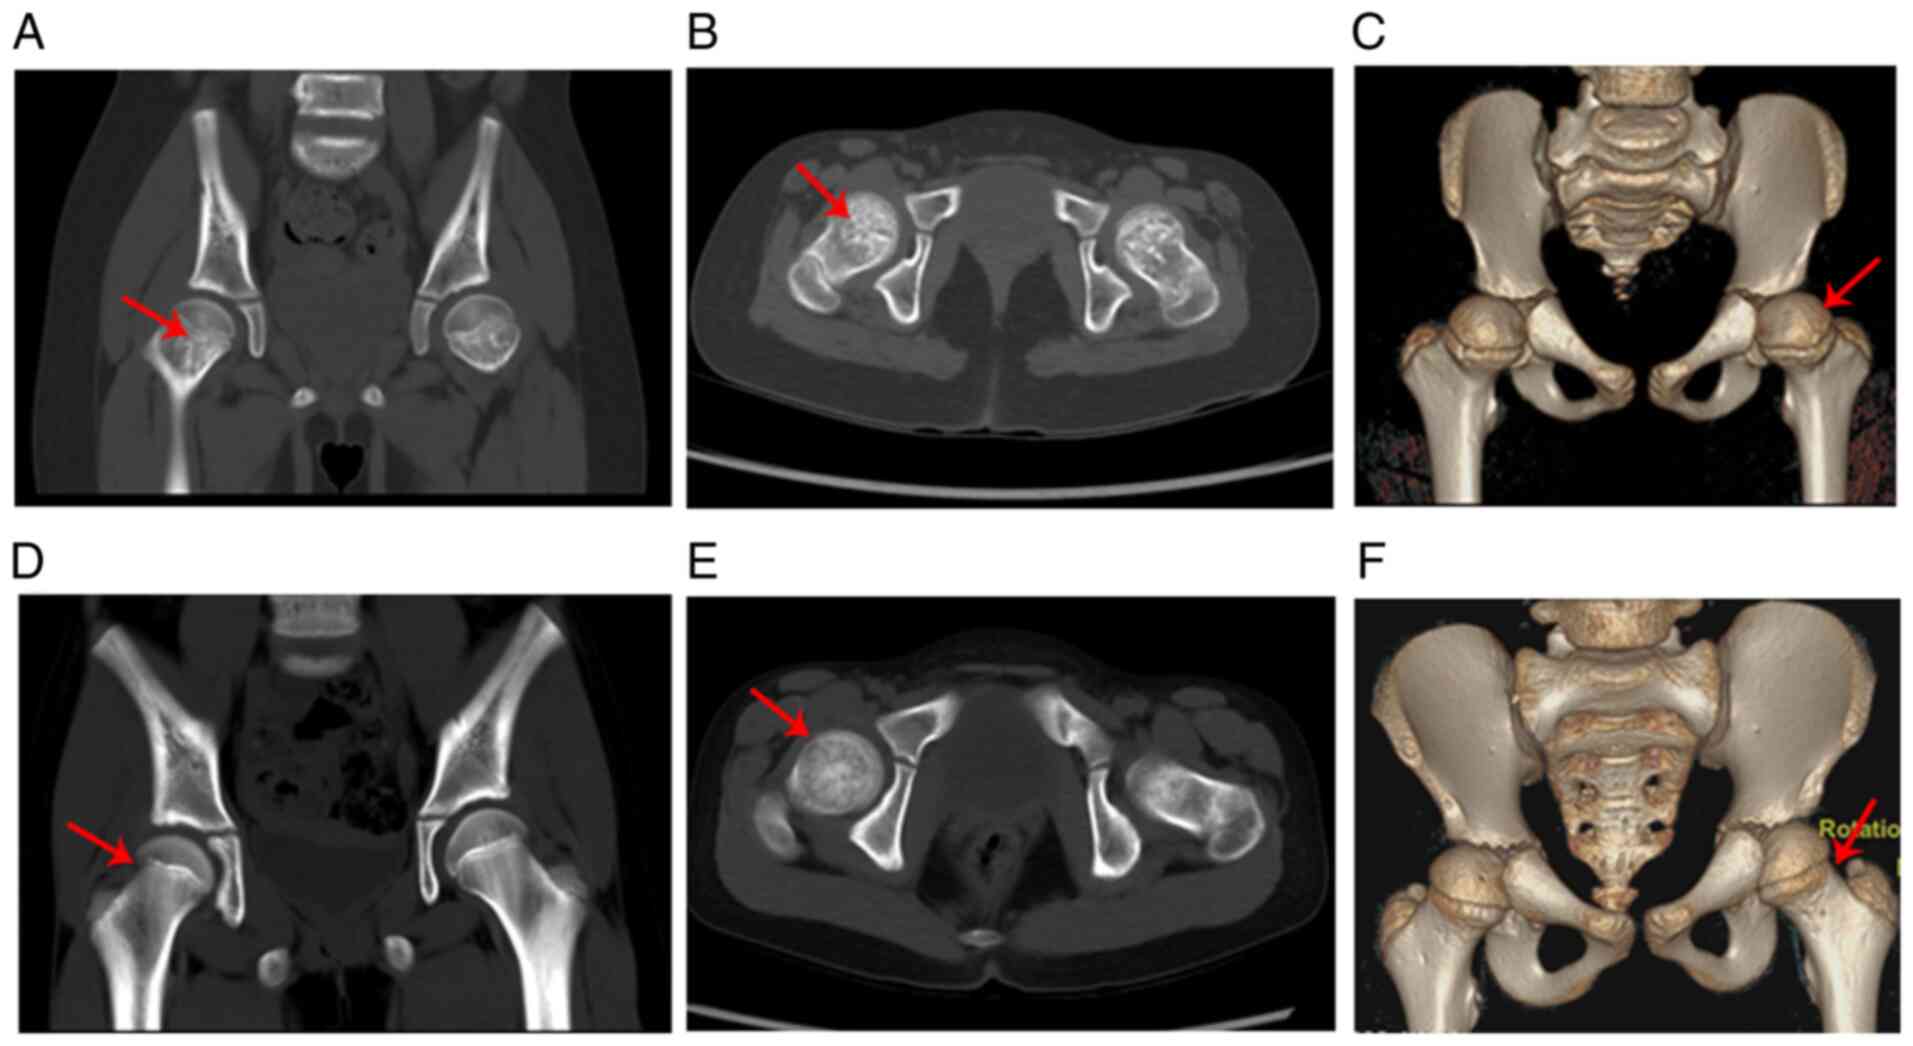

At the age of 7 years and 8 months, the patient was subjected to spiral computed tomography (CT) and the results showed that the bone density of the femoral neck was uneven (patchy high or low density) and that the femoral neck was thicker and shorter than those of the age- and gender-matched control (Fig. 4A-F). The three-dimensional double-echo steady state with water excitation MRI of the hip further revealed that the thickness of the proximal femoral epiphyseal plate was uneven and that the metaphysis of the proximal femur showed a stripe-like hyperintensity (such hyperintensity was continuous to the adjacent epiphyseal plate) (Fig. 5A-C). Fig. 5D shows the normal hip MRI of the age- and sex-matched control in coronal view. The three-dimensional volume rendering of the cranium identified the disproportionate cerebral and facial cranium as trigonocephaly, and the brain CT scan showed that the bilateral frontal extracerebral space was widened (Fig. 5E and F). The brain MRI indicated that the sella was flat and exhibited hook-like changes (Fig. 5G).

Figure 4.

Spiral CT image of the hip. (A) Coronal and (B) transverse axis views demonstrate an uneven density (patchy high or low density) of the femoral neck as indicated by the red arrows. (C) Three-dimensional volume rendering revealed that the femoral neck was short and thick as indicated by the red arrow. (D-F) Normal hip spiral CT of an age- and sex-matched control. CT, computed tomography.